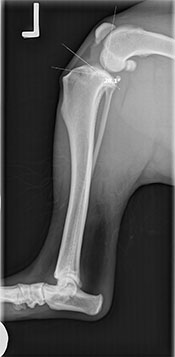

A thorough physical examination showed signs of positive cranial drawer and tibial thrust (unnatural movement) in the right knee. He was sedated and radiographs were taken, which showed arthritic changes in both his knees.

Dr. Edinger diagnosed him with bilateral cranial cruciate ligament (CCL) tears; completely torn on the right, and partially torn on the left. Due to Fen’s active lifestyle and the arthritis that was already present in both knees, Fen’s people elected to pursue bilateral Tibial Plateau Leveling Osteotomies (TPLO’s) to correct the instability in both of his knees.